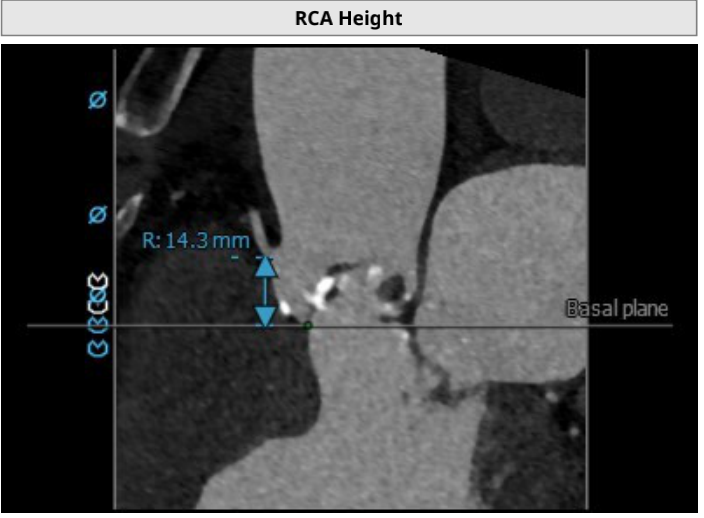

左冠开口高度5.2mm;右冠开口高度14.3mm。左冠开口低,瓣叶稍长,术中需球扩确认冠脉风险。

3.患者左侧冠脉开口高度低LCA:5.2mm,左冠瓣瓣叶长度约16.7mm;右侧冠脉开口高度可RCA:14.3mm。